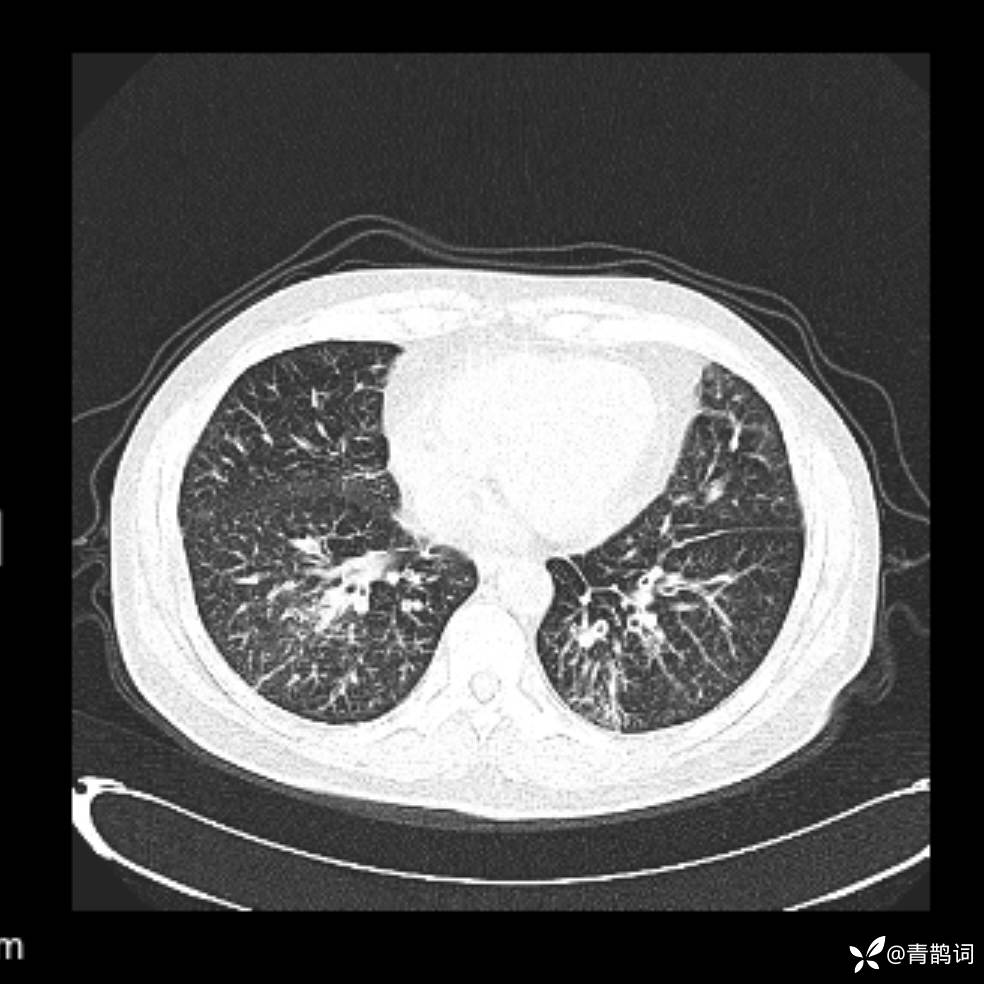

患者年龄:30岁。

患者性别:男。

简要病史:左颜面部肿胀2年,反复咳嗽咳痰,逐渐加重。

辅助检查

结合病史及影像学表现,期待评论区各位老师各抒己见~